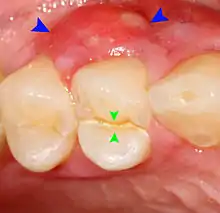

| Cross-section of a posterior tooth. | |